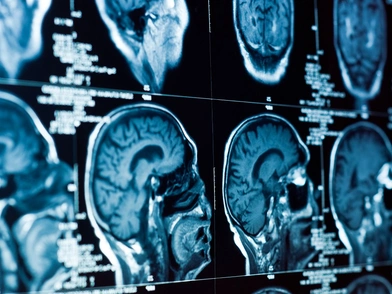

Ο μεγαλύτερος ενδοκρινής αδένας του ανθρώπινου σώματος, με βασική λειτουργία την ρύθμιση του μεταβολισμού, είναι ο θυρεοειδής. Ωστόσο, επιδρά σε κάθε όργανο, διασφαλίζοντας πλήθος λειτουργιών, από την φυσιολογική ανάπτυξη του εγκεφάλου, έως την κατανάλωση ενέργειας και την παραγωγή θερμότητας.

Για να επιτελέσει αυτές τις λειτουργίες ο θυρεοειδής, λαμβάνει εντολές από τις εγκεφαλικές περιοχές της υπόφυσης, μέσω της θυρεοτρόπου ορμόνης (TSH), και έμμεσα από τον υποθάλαμο μέσω της εκλυτικής ορμόνης της θυρεοτρόπου ορμόνης (TRH), σχηματίζοντας τον άξονα Υποθάλαμο-Υπόφυση-Θυρεοειδής, που ελέγχει την λειτουργία του θυρεοειδούς αδένα. Το όνομά του προέρχεται από το σχήμα του (θυρεός ή ασπίδα).